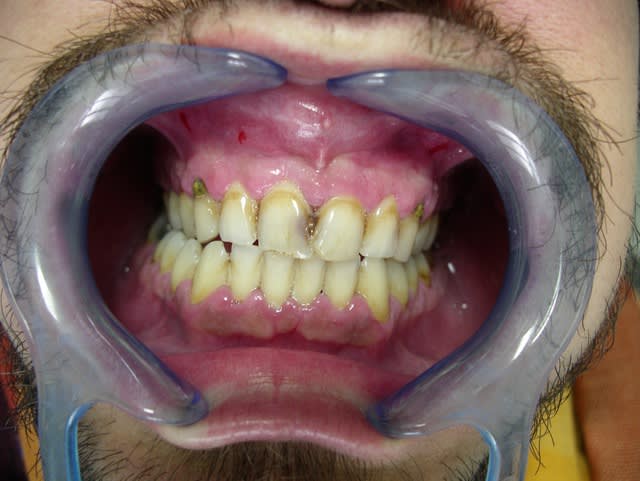

Déjà il faut savoir que la méthadone est TRES sucrée. Donc cela augmente le risque de carie chez des patients dont on sait déjà que l'hygiène n'est pas là et où il y a déjà beaucoup de caries.

Ensuite, effectivement, les réactions aux anesthésies sont plus longues. Les caries se développent rapidement avec énormément de caries du collet.

http://en.wikipedia.org/wiki/Meth_mouth

un lien sur la "meth mouth" consécutive à la consomation de métamphétamine surtout présente outre-atlantique.